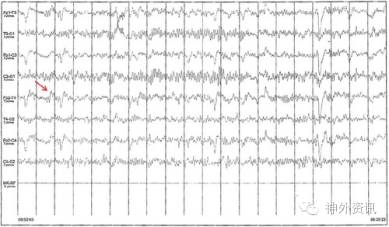

11岁女性患者,出生时借助产钳分娩导致双侧顶部头颅血肿。产后1月左右左侧血肿基本吸收,右侧血肿逐渐钙化,当时医生没有建议手术。女孩成长过程中没有出现与血肿相关的躯体或神经精神方面的问题。然而,神经心理测试发现有学习上的障碍,包括轻度的注意力不集中。为此,进行脑电图检查(EEG),当时没有显示异常。10岁左右的随访EEG中出现不对称α波活动背景下的右侧额顶部低振幅、散在的棘波(图1)。头颅MRI检查提示,右顶部头颅血肿,厚度25mm,伴有颅骨内层改变和脑实质中度受压(图2)。3月后复查EEG的结果同前。患儿有轻度头痛,并要求美容手术。

图1. 术前EEG显示不对称的脑电活动背景下右侧额顶部散在棘波。